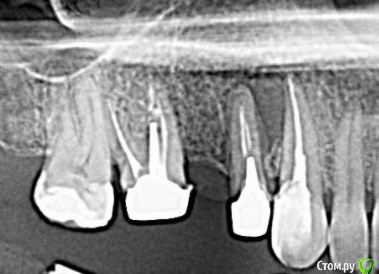

полосатая Опубликовано 3 августа, 2016 Поделиться Опубликовано 3 августа, 2016 (изменено) Здравствуйте.Обратилась к стоматологу по поводу свища- гранулемы между 3-м и 4-м зубами справа на верхней челюсти.Примерно 3 месяца ходила на лечение,закладывали кальций+йод.Сейчас зубы подготовлены под протезирование(пока временное ) с пластмассовым мостом.Каналы заполнены гуттаперчей,зафиксированы вкладки.Есть сомнения по поводу качества пломбирования каналов и фиксации вкладок: Прошу оценить качество работы. Может, пока на поздно нужно переделать?Зубы очень хочется сохранить.Фрагмент панорамного снимка: Изменено 3 августа, 2016 пользователем полосатая Ссылка на комментарий

полосатая Опубликовано 3 августа, 2016 Автор Поделиться Опубликовано 3 августа, 2016 Фрагмент панорамного снимка на момент обращения. Ссылка на комментарий